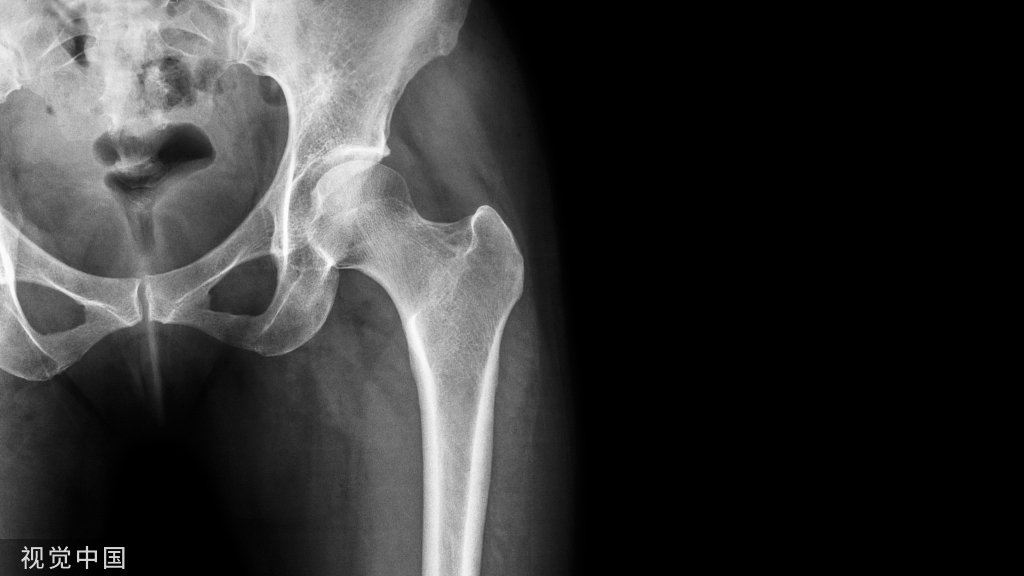

说到髌骨脱位,首先就要了解髌骨,髌骨是人体最大的籽骨,倒三角状位于膝关节前方,它的上缘与股四头肌腱相连,下缘通过髌韧带止于胫骨结节上,两侧为股四头肌扩张部,髌骨后方的凸面为光滑的关节面,与股骨下端内外髁之间的滑车凹面关节面形成关节。尽管股四头肌中的股直肌、股中间肌、股外侧肌的作用方向与髌韧带不在一条直线上,髌骨有向外突出的倾向,但因股内侧肌有向内上方牵拉作用力而使髌骨维持在正常位置。

髌骨脱位绝大部分是向外侧脱位,脱位后,髌股关节内侧的稳定结构,包括髌股关节内侧支持带、股内侧肌、内侧髌股韧带均被撕裂,导致膝关节腔内积肿,在髌骨脱位以及自行复位的过程中,髌骨内侧面与股骨髁外侧面撞击,会引起软骨损伤或骨软骨骨折,所以,千万不要把髌骨脱位当作成一个简单的疾病。

DR检查包括下肢全长正位片、侧位片、膝关节正侧位、髌骨切线位等,有助于评估膝关节力线及滑车的形态,髌骨高度、髌骨倾斜,关节病等信息。

MRI检查是最常用的评估髌股关节软组织和滑车软骨的检查,在发现MPFL损伤时具有较高的敏感性和准确性,其特征性表现包括X线不能发现的软骨损伤及髌骨内侧面和股骨外侧髁的骨挫伤。MRI也可用于评估髌骨滑车指,测量髌骨高度等。